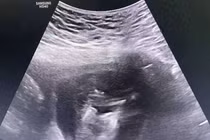

Thai phụ Nguyễn T. H. (34 tuổi trú tại Gia Lâm, Hà Nội) mang song thai IVF 29 tuần 2 ngày, nhập viện khu điều trị thai phụ mắc Covid-19 tại Cơ sở 2, Bệnh viện Phụ sản Hà Nội ngày 11/12/2021, xét nghiệm dương tính với SARS-CoV-2 với nồng độ virus khá cao.

Bệnh viện Phụ sản Hà Nội đã nghiên cứu và ứng dụng kỹ thuật phẫu thuật nội soi vào buồng ối, chữa bệnh trong bào thai nhằm lập lại cân bằng dinh dưỡng giữa hai em bé, để hai thai có thể phát triển tiếp.

Truyền 40ml khối hồng cầu trực tiếp vào thai nhi bị thiếu máu thông qua tĩnh mạch rốn đã cứu sống hai thiên thần nhỏ có nguy cơ mất thai ở tuần thứ 29.